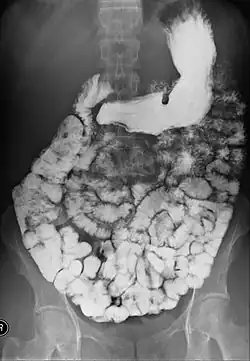

- Barium follow-through examinations are used to study the small intestine.[2]

X-ray images are then taken in a supine position at intervals of 20–30 minutes. Real-time fluoroscopy is used to assess bowel motility. The radiologist may press or palpate the abdomen during images to separate intestinal loops. The total time necessary for the test depends on the speed of bowel motility or transit time and may vary between 1 and 3 hours.[17]

- Barium follow-through examinations are the most commonly used imaging technique in assessing patients with Crohn's disease, although CT and magnetic resonance imaging are widely accepted as being superior.[1] However Barium examinations remain superior in the depiction of mucosal abnormalities.[24] The features of Crohn's disease are well described by barium follow-through examinations, appearing as a typical "cobblestone pattern", but no information is obtained regarding extraluminal disease.[28] Radiographic imaging in Crohn's disease provides clinicians with objective evaluations of small bowel regions that are not accessible to standard endoscopic techniques.[29] Because of its length and complex loops, the small intestine is the most difficult part of the gastrointestinal tract to evaluate. Most endoscopic techniques are limited to the examination of proximal or distal segments, hence Barium follow-through remains in most centres the test of choice for the investigation of abdominal pain, diarrhoea and in particular diseases manifesting mucosal abnormalities such as coeliac and Crohn's disease.[26]